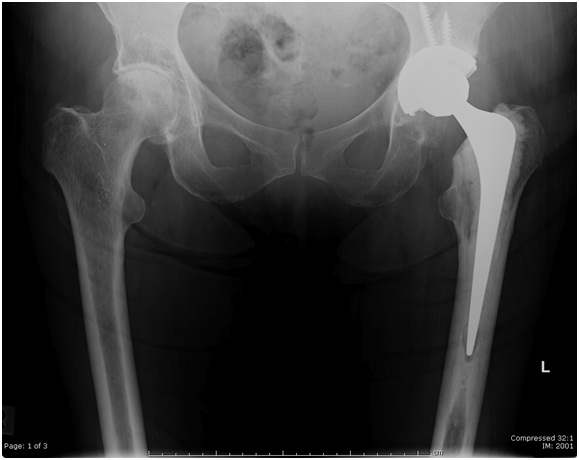

The operation takes around 1 ½ hours to perform. A cut around 15-20 cm long is made and the old hip is cut out. The new hip replacement comprises two main parts. There is a stem or metal rod which sits inside the thigh bone (femur) and has a ball on the end of it. It is designed to either be cemented into place or have the bone grow onto it to hold it in place. The second part is a cup which sits in the pelvis. It can either be a piece of plastic cemented into place or a metal shell which is hit into place and allows bone to grow onto it. There are potential advantages and disadvantages of different sorts of hip prostheses (replacements). Your surgeon will discuss with you which one they think will be best for you.